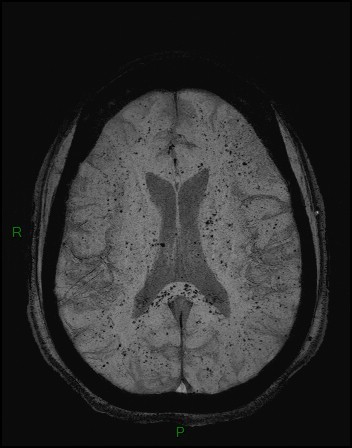

Note the multiple sites of oedema and haemorrhage, involving the brain stem and corpus callosum as well as subcortical white matter and left cerebral peduncle. High FLAIR signal is also seen in the dorsal midbrain. EVD insitu.

Case Discussion

Diffuse axonal injury can be subtle on CT but have devastating consequences for the patient. This is a case of grade III injury (involvement of brainstem) and carries a poor prognosis.

Diffuse axonal injury (DAI), also known as traumatic axonal injury (TAI), is a severe form of traumatic brain injury due to shearing forces. It is a potentially difficult diagnosis to make on imaging alone, especially on CT as the finding can be subtle, however, it has the potential to result in severe neurological impairment.

The diagnosis is best made on MRI where it is characterised by several small regions of susceptibility artifact at the grey-white matter junction, in the corpus callosum, and in more severe cases in the brainstem, surrounded by FLAIR hyperintensity.

Diffuse axonal injury is characterised by multiple focal lesions with a characteristic distribution: typically located at the grey-white matter junction, in the corpus callosum and in more severe cases in the brainstem (see: grading of diffuse axonal injury).

MRI is the modality of choice for assessing suspected diffuse axonal injury even in patients with entirely normal CT of the brain 5,6. MRI, especially SWI or GRE sequences, exquisitely sensitive to paramagnetic blood products may demonstrate small regions of susceptibility artefact at the grey-white matter junction, in the corpus callosum or the brain stem. Some lesions may be entirely non-haemorrhagic (even using high field strength SWI sequences). These will, however, be visible as regions of high FLAIR signal.